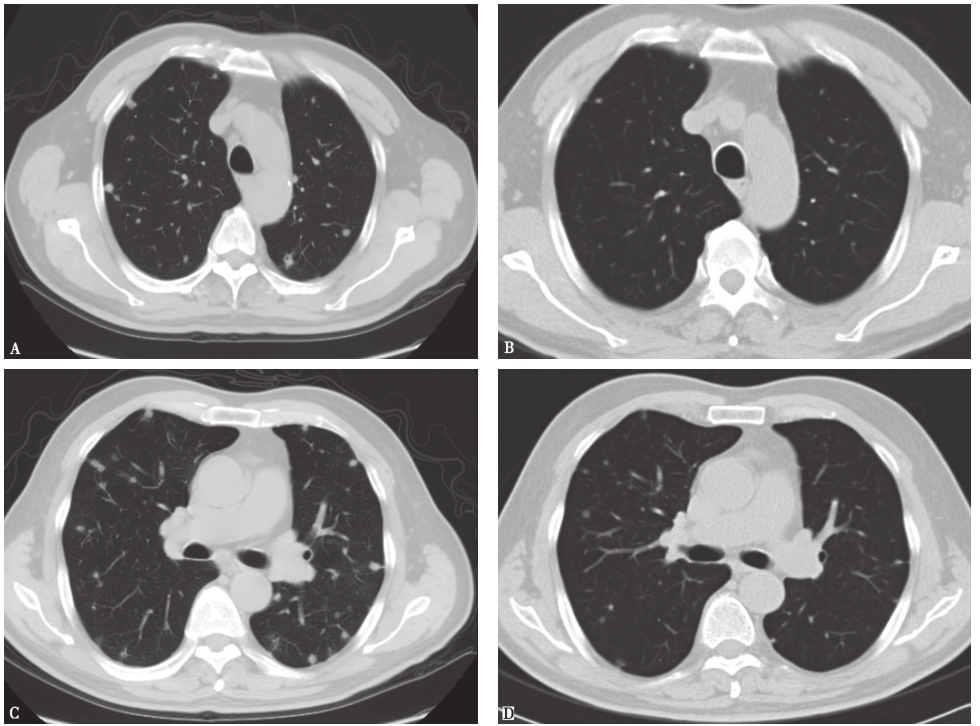

2013年3月5日复查胸部CT示双肺结节影,伴多发纤维索条样病变(图2)。

图2病例Ⅰ胸部CT表现(2013-03-05)

病例Ⅰ入院后体温正常,咳嗽、气短症状较前好转,于2013年8月24日复查胸部CT,见肺部病变较前明显吸收(图4);病例Ⅱ口服伊曲康唑1个月后出现甲状腺功能低下而停用,发病7个月后复查胸部CT,见双肺结节亦明显吸收(图5)。

图4病例Ⅰ治疗后复查胸部CT表现

2013年3月5日查胸部CT(A、C、E)示双肺多发结节性病变伴纤维索条影;2013年8月24日复查胸部CT(B、D、F)示双肺结节样病灶较前明显吸收